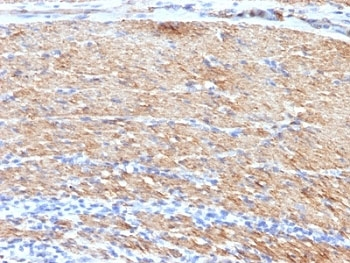

IHC: Formalin-fixed, paraffin-embedded human colon carcinoma stained with SMMHC antibody (MYH11/923).